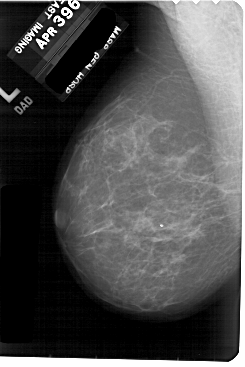

A_1886_1.LEFT_MLO

LEFT_MLO LINES 5491 PIXELS_PER_LINE 3661 BITS_PER_PIXEL 12 RESOLUTION 43.5 NON_OVERLAY